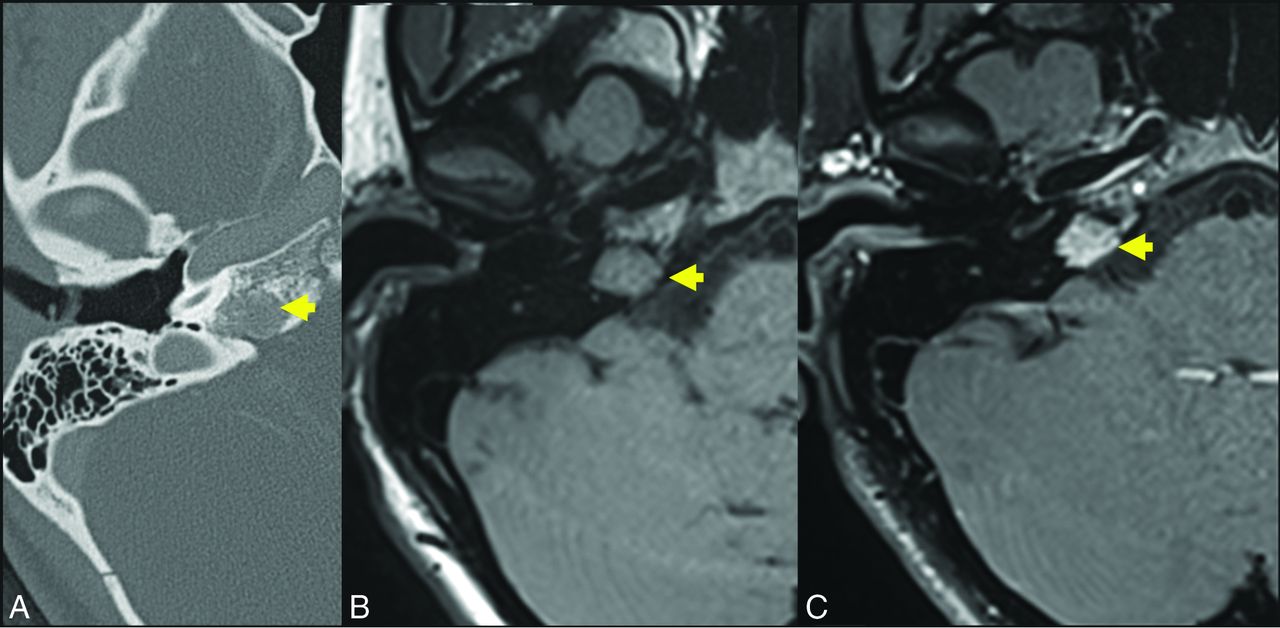

A 17-year-old girl referred for suspicion of paraganglioma identified incidentally on head CT for trauma. Axial thin-section CT (A) demonstrates a hypodense lesion centered in the right petrous apex (yellow arrow). The presence of internal trabeculae in a honeycomb pattern as well as the lesion location differentiate the correct diagnosis (IOVM of the skull base) and the suspected diagnosis of glomus jugulare paraganglioma. Axial T1 C– (B) and axial T1 C+ (C) sequences through the skull base demonstrate that the lesion is T1-intermediate (yellow arrow, B) and avidly enhancing (yellow arrow, C). A diagnosis of IOVM was made on the basis of characteristic imaging appearance. C+ indicates with contrast; C–, without contrast.